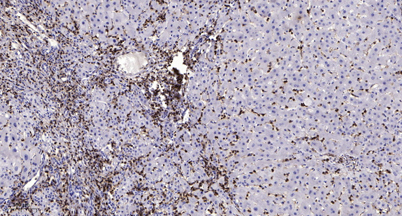

Product name: MSK1 (phospho Ser376) rabbit pAb

Dilutions: WB 1:500-2000;IHC-p 1:50-300

Immunogen: The antiserum was produced against synthesized peptide derived from human MSK1 around the phosphorylation site of Ser376. AA range:343-392